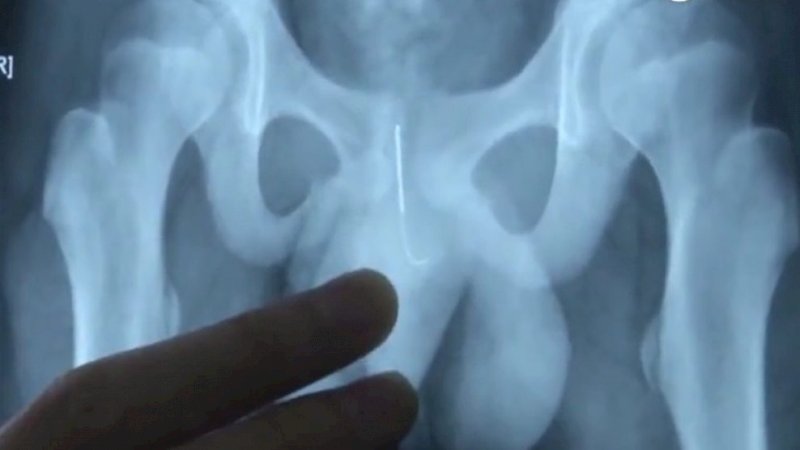

Dia mengambil jarum akupunktur neneknya dan menusukkannya ke uretra melalui kemaluannya.

Ketika ditanya, anak itu baru mengaku telah menusuk dirinya dengan jarum 10cm agar tidak ketiduran.

Dia pun segera dibawa ke rumah sakit dan menjalani operasi.

Dokter mengatakan bahwa mencabut jarum suntik itu berisiko menimbulkan kerusakan dan infeksi.

Jadi, dia terpaksa harus dioperasi. Prosesnya memakan waktu dua jam, dan jarum itu telah dikeluarkan dengan aman.